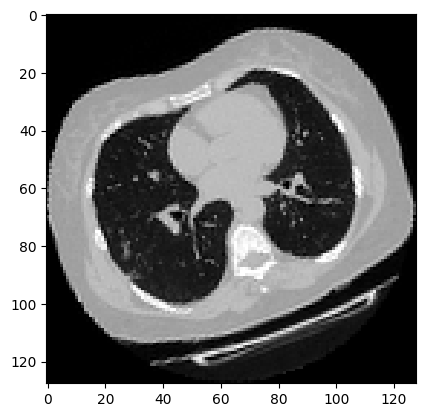

可视化增强型 CT 扫描。

images, labels = train_dataset.__getitem__(0)

print(images.shape)

image = np.squeeze(images, 3)

print("Dimension of the CT scan is:", image.shape)

plt.imshow(np.squeeze(image[:, :, 30]), cmap="gray")

plt.show()

(128, 128, 64, 1)

Dimension of the CT scan is: (128, 128, 64)